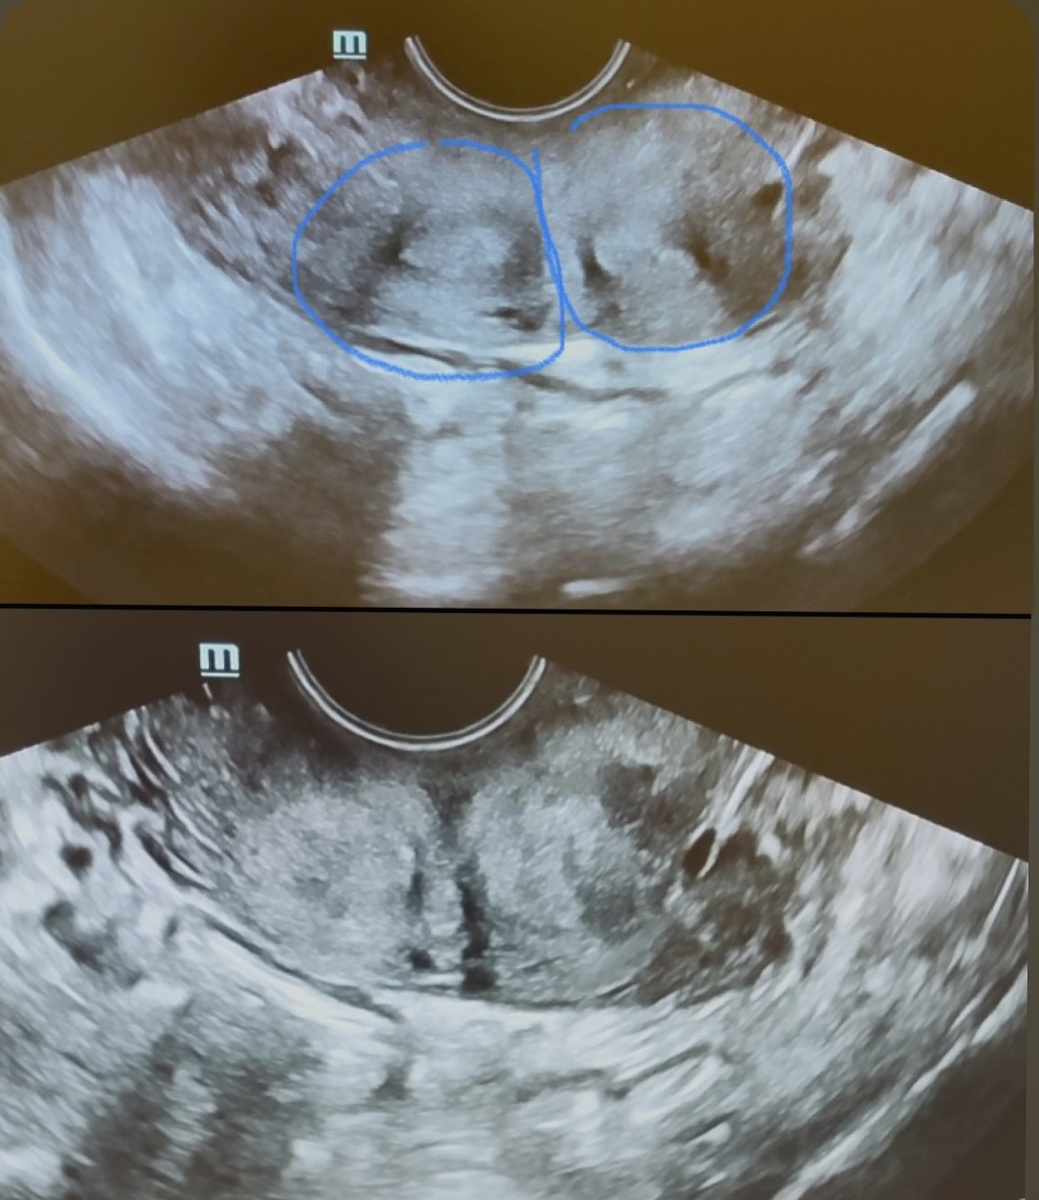

—Две матки — это редкая аномалия развития. Я в своей практике вижу такое второй раз, а конкретно на УЗИ — это впервые. Были и двурогие, и седловидные, с перегородками — но чтобы прямо две матки — такого не было.

Две матки, поперечный срез. Фото автора.